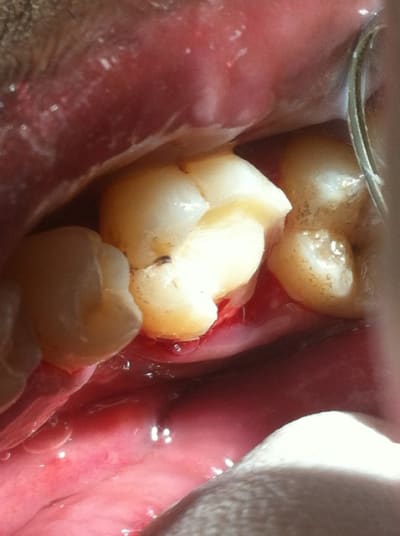

Ben alors j'ai un cas là justement : je fais quoi? Onlay ou Couronne?

Dent vivante, CVI renforcé après la taille en coiffage attente de 3 semaines avec pansement pour être sûr, RAS dent toujours vivante quand je l'ai revu aujourd'hui.

Aujourd'hui : retouche du CVI puis (première photo au stade du mordançage) compo pour le core build-up, pansement.

Les photos sont pas top mais pour le moment je fais avec ce que j'avais sous la main...

Qu'est-ce que je fais pour la suite du coup? Onlay ou Couronne?

PS. On ne voit pas bien la différence à la radio avant-après... Désolé.

Perso je penche pour la couronne...